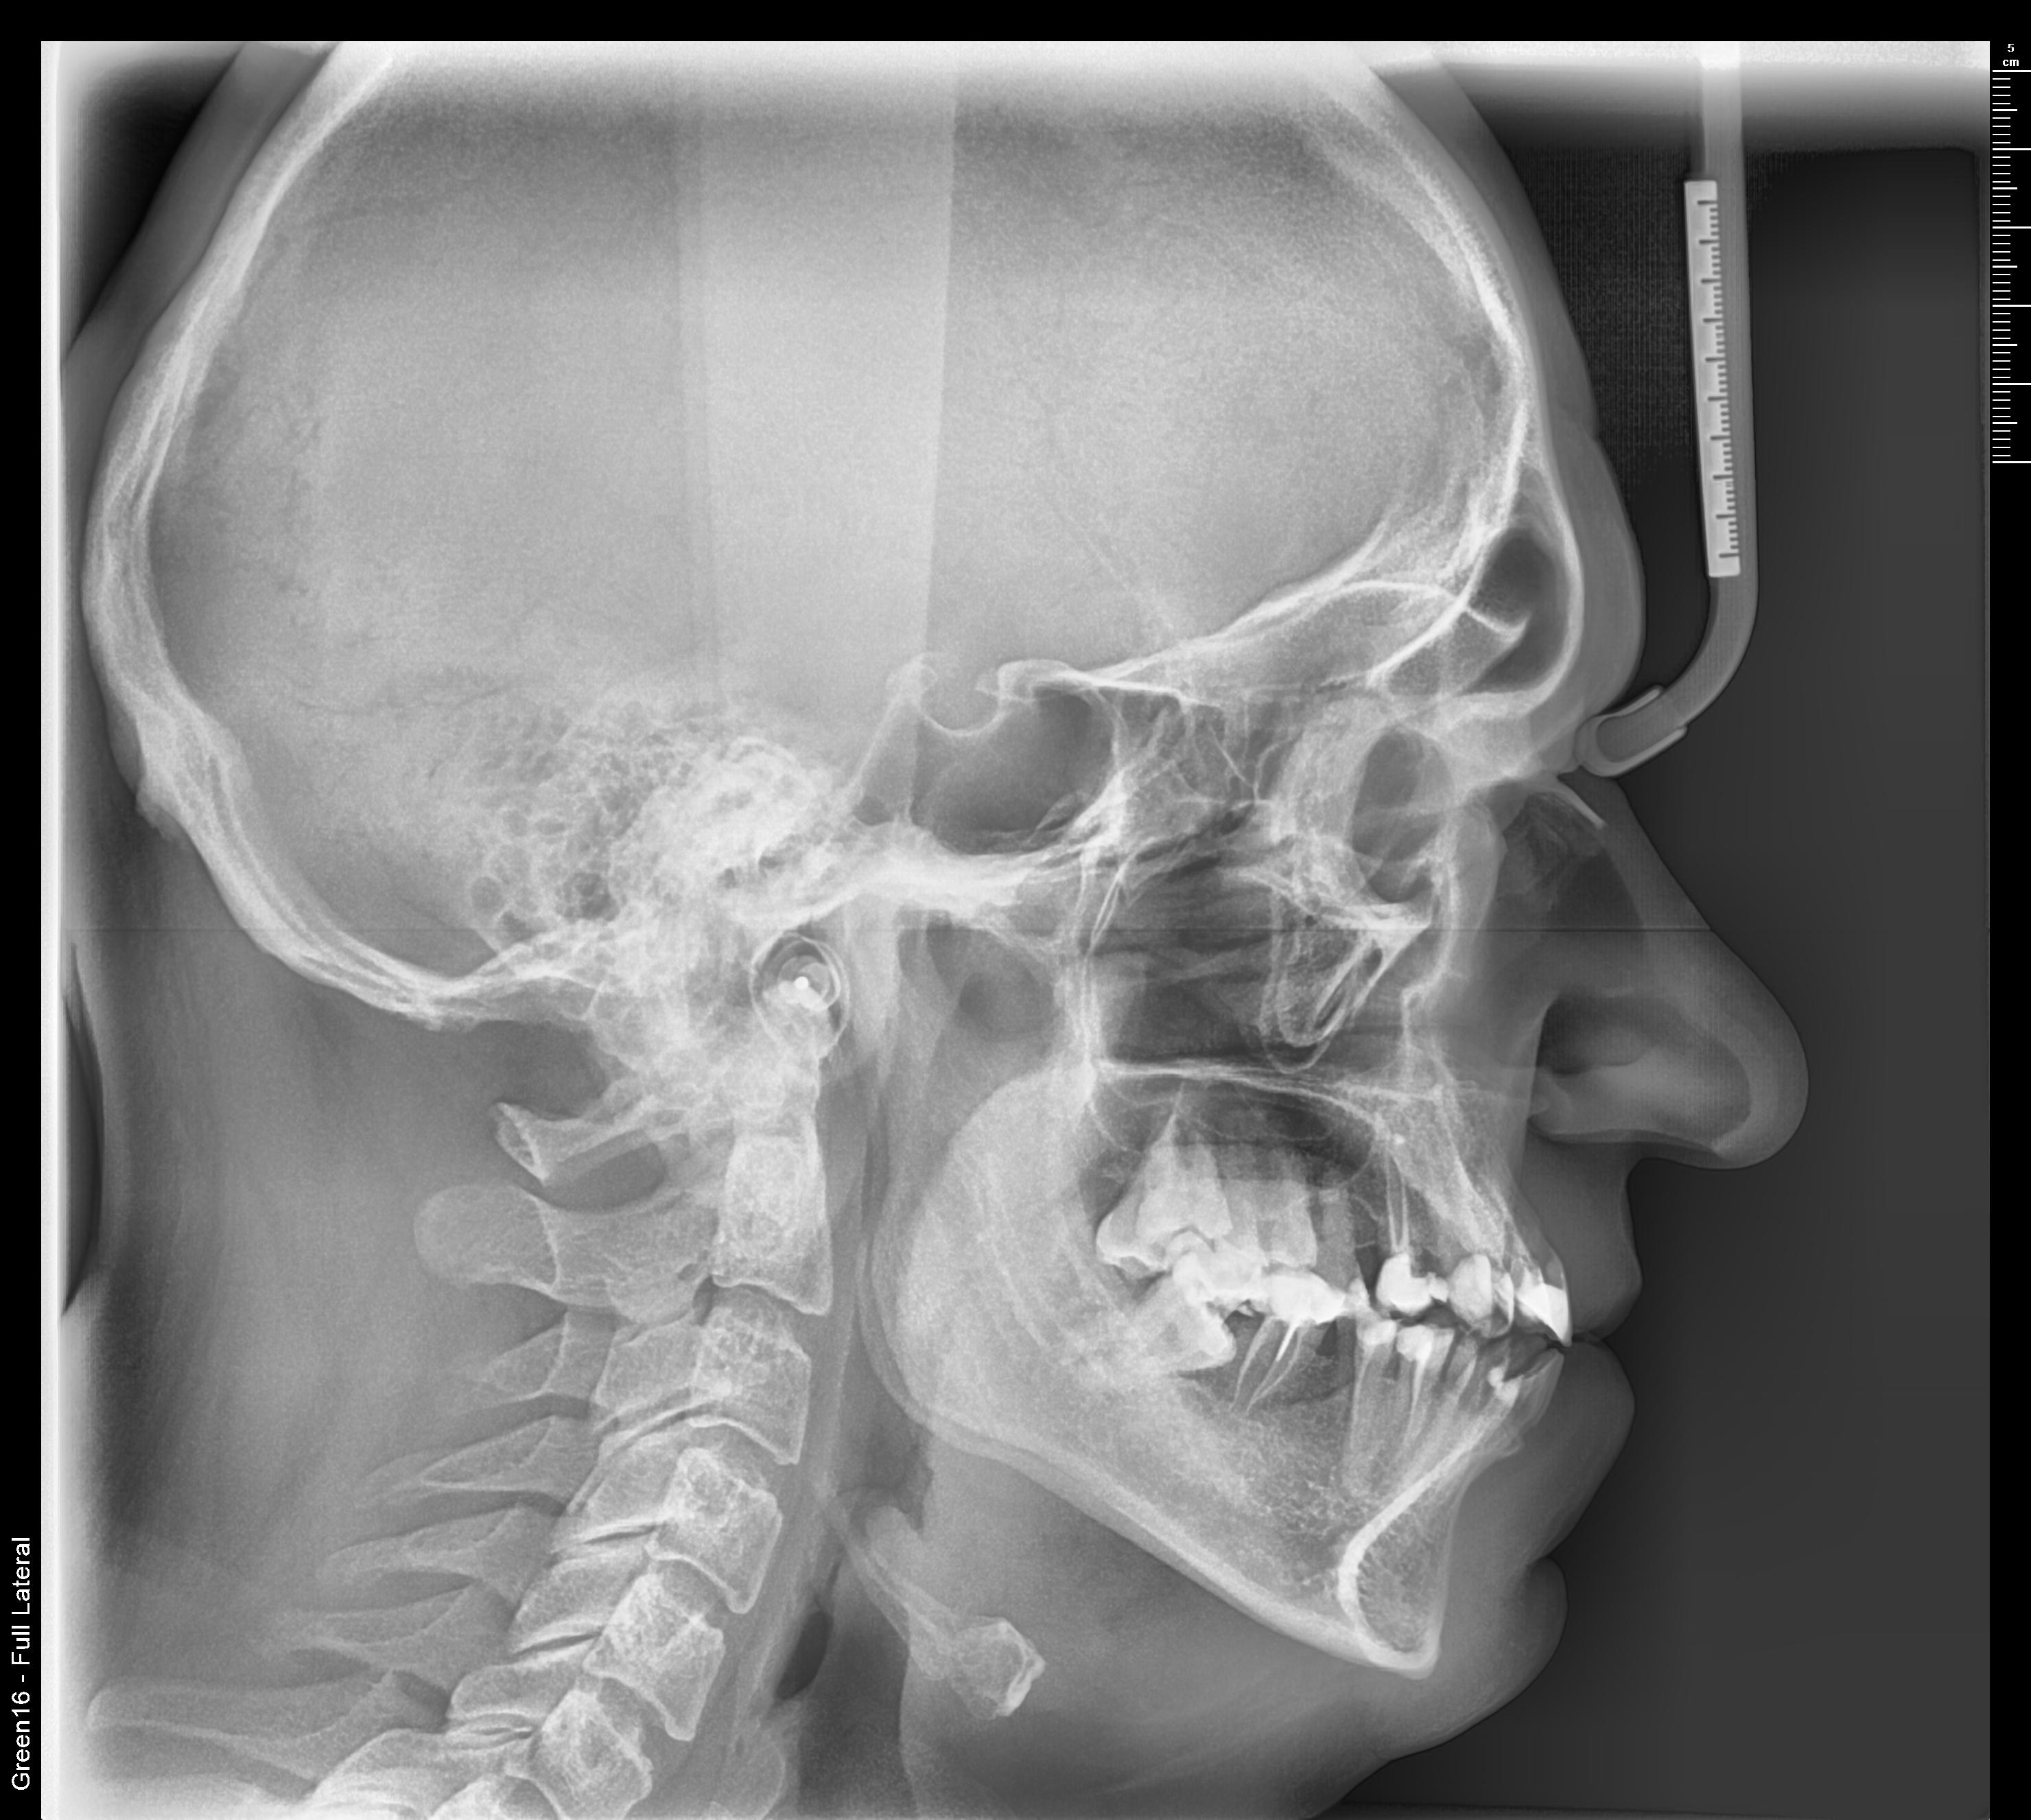

Телерентгенограмма — что это такое?

ТРГ зубов — это 2D рентген-снимок черепа, который позволяет увидеть, как расположены корни зубов, челюсти пациента. Он дает понимание, в каком состоянии находятся костные и мягкие ткани исследуемой части лица.Ортопантомограф создает изображения на расстоянии 1.5-2 метра. За счет этого они получаются в естественных пропорциях с минимальными искажениями.

Боковая (латеральная) проекция: позволяет оценить соотношение челюстей, наклон зубов и выявить аномалии прикуса. Часто используется для планирования и контроля ортодонтического лечения;